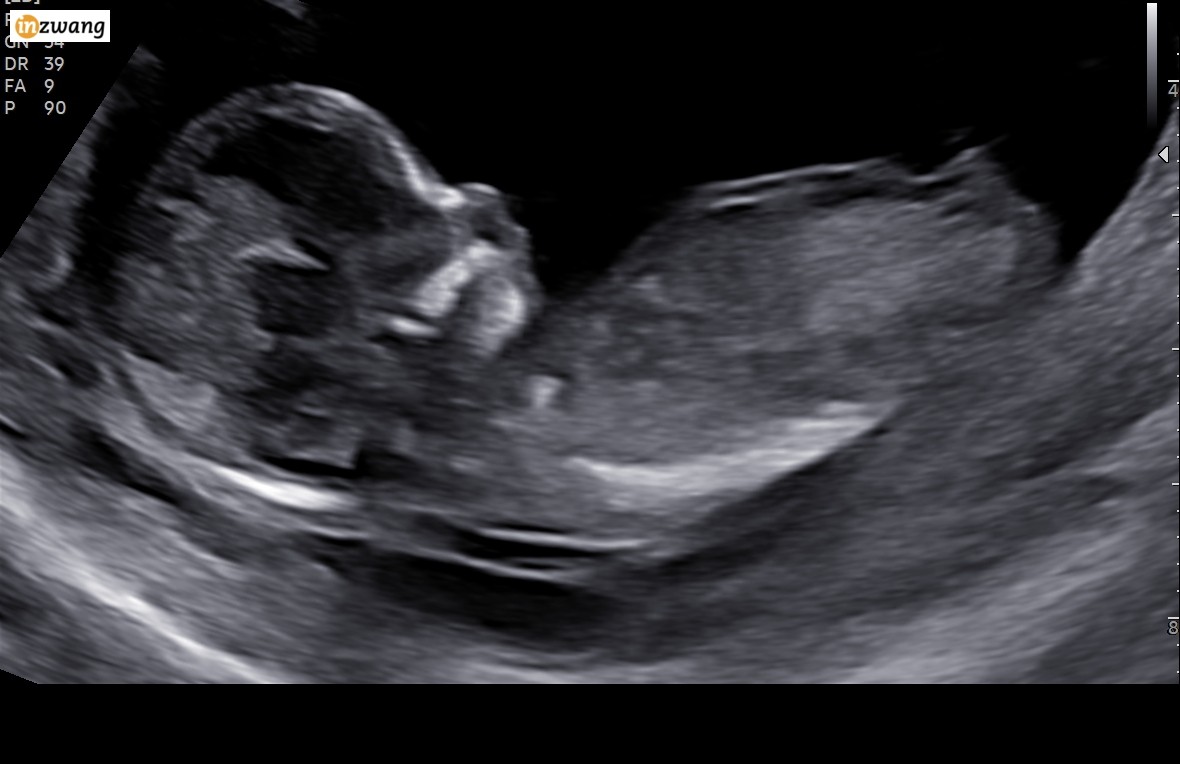

Jak sądzicie, chłopak, czy dziewczynka? Mam swoje podejrzenie. Wiek: 13+1. Niestety w trakcie tego badania, w Holandii, nie mówią jaka płeć, nawet jeśli zobacza

Załączniki

• 639276966.jpg

639276966.jpg

101,6 KB · Wyświetleń: 326